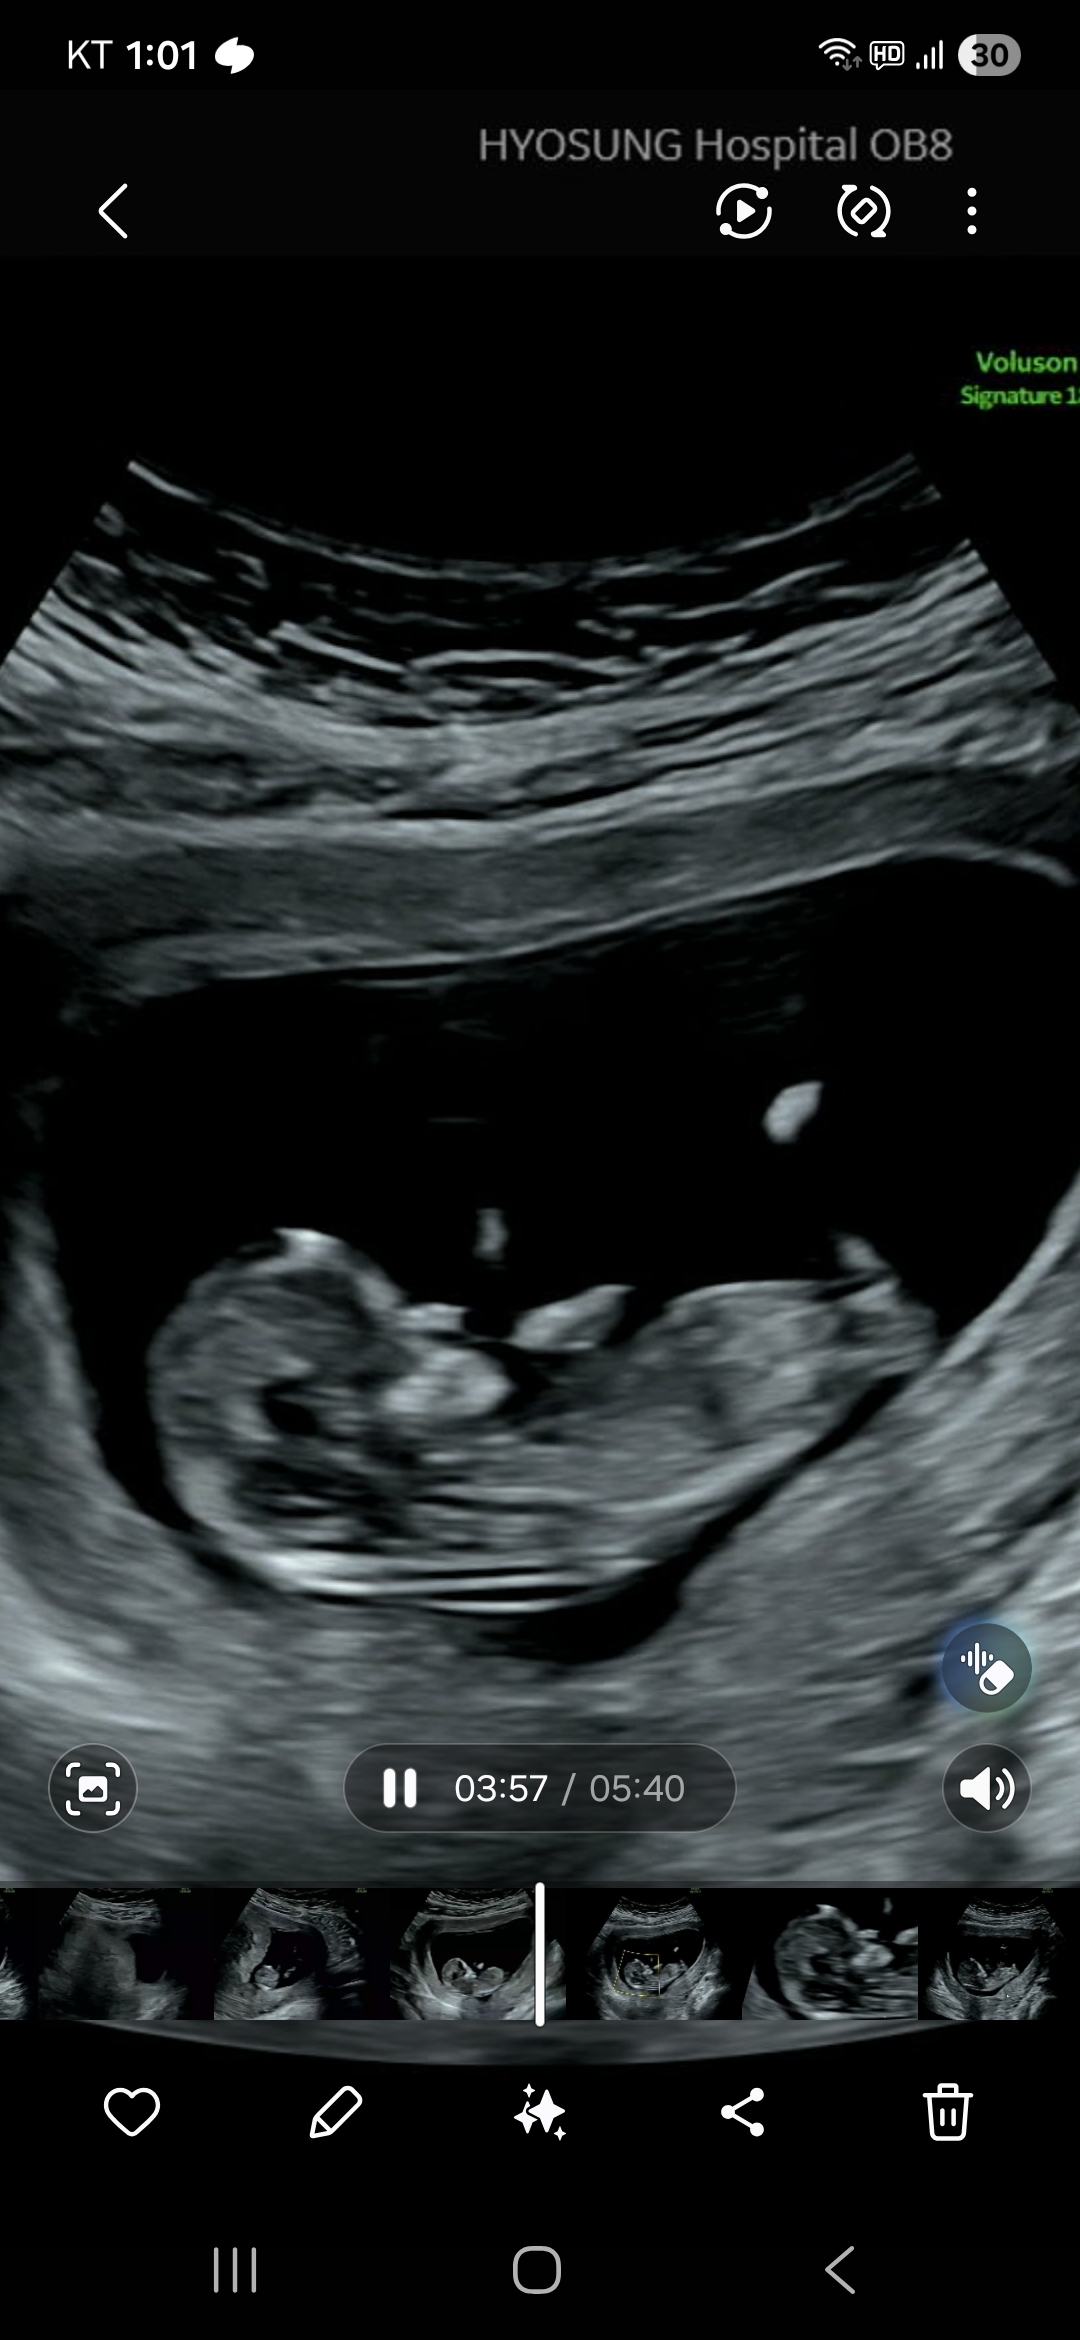

안녕하세요. 12주 1일차 된 토깽이 맘입니다. 어제 초음파로 정밀 검사하고 코뼈, 목투명대 정상으로 기형아 검사를 따로 하지 않았는데요. 병원을 나서고 보니, 니프티는 안해도 기형아 검사는 해볼껄 그랬나? 생각이 들더라구요. 혹시 저처럼 기형아 검사를 진행하지 않으신 분이나, 기형아 검사 진행하지 않았는데 정상으로 결과 나오신 분들 있을까요?? 그리고 각도법으로 아들인지 딸인지도 너무 궁금해요!! 답변 부탁드려요~^^